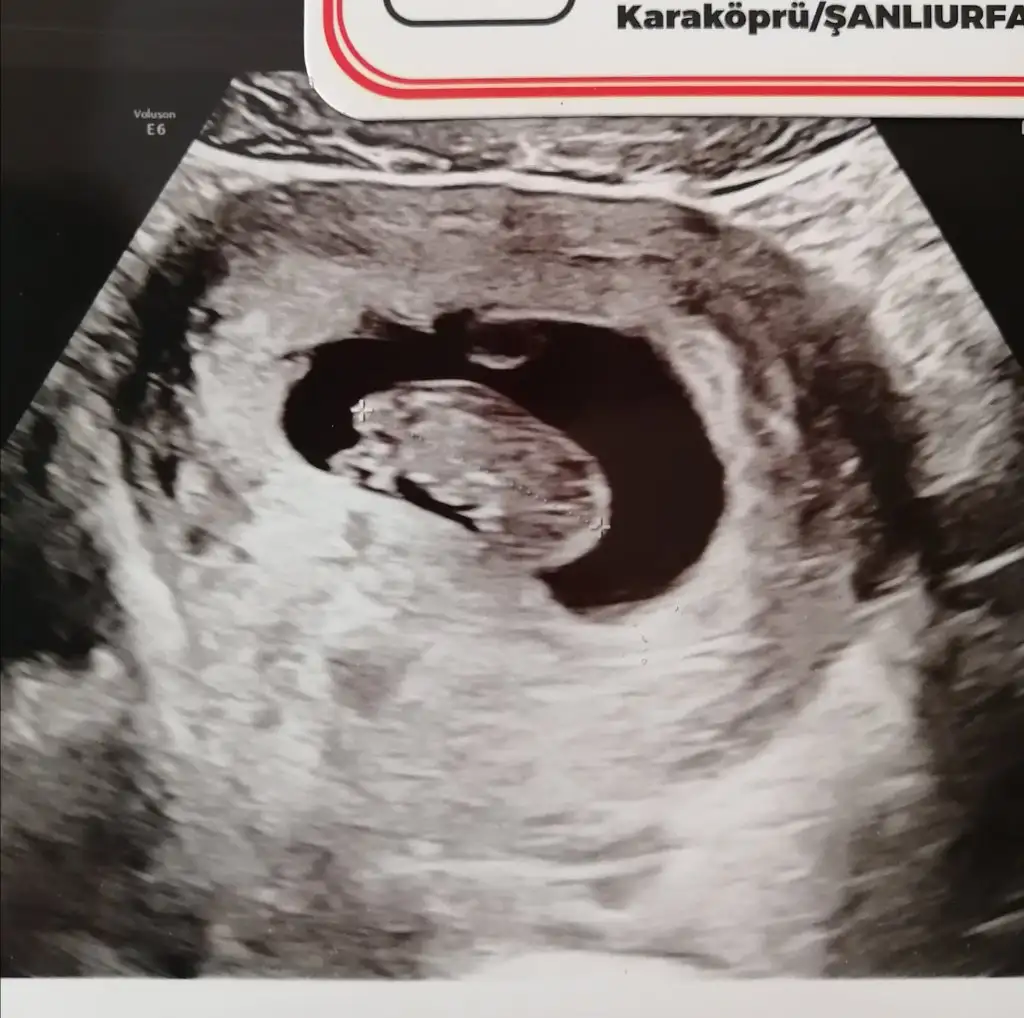

Ne kdr buyumus canim masallah ona, kareye sigmadigi gunleri de saglikla gorelim

Alttan mi bakmıştı canım karından mi sana ?Benim zannediyorum sizden kucuk canim, sat 20 ocak transfer de 4 subatta oldu, gordugumde 5+6 demisti dr, biz kese gormeye gtmsken supriz oldu ne video be bisi hicbisi gelmedi aklimiza, dr 2 hfta snra gelin dedi ama bana gunler gecmiyor